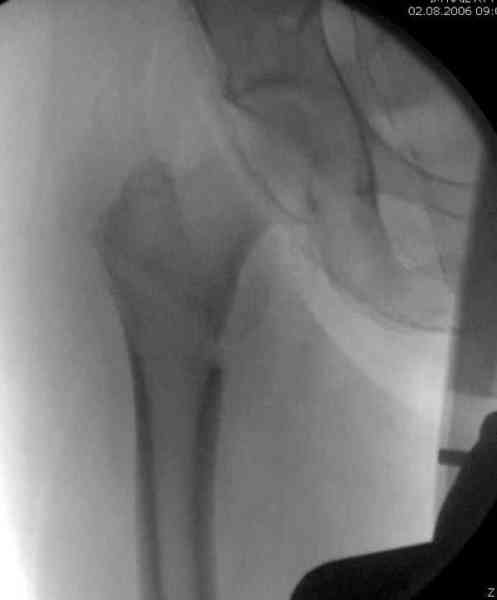

Здесь сканнированные снимки импланта и операционные снимки больной.

На этом снимке процесс компрессии нижним болтом.

Итог